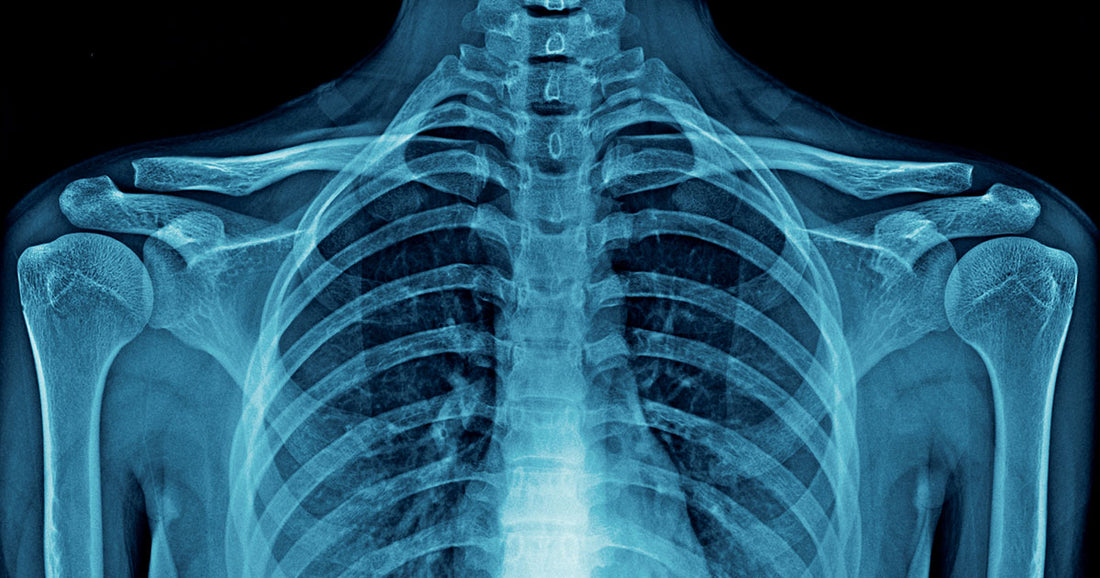

The bones in the human body do so much work. Besides holding the body's weight, bones also protect the brain, heart, and other vital organs from harm and injury. Impacts of accidents and rigorous physical activity to the organs are less severe because of bones that cage them.

Also, bones serve as the storage facility for minerals needed in the body, such as calcium and phosphorus. These minerals are released when the need arises.